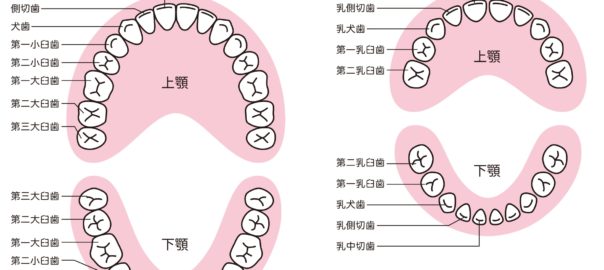

- 2020/12/22 永久歯の本数、乳歯の本数

こんにちは、静岡市駿河区にある歯科医院、小嶋デンタルクリニックです。 先日、大人の歯は全部で何本ありますか?と質問を受けました。 また子供を持つお母さんに、乳歯は全部で何本ありますか?と聞かれ … 続きを読む 永久歯の本数、乳歯の本数

→ 続きを見る

- 2020/10/10 乳歯から永久歯の交換期について

こんにちは、静岡市駿河区にある歯科医院、小嶋デンタルクリニックです。 本日は、乳歯から永久歯への生え替わりについてご説明します。 よくご質問をいただくことが多い内容です。 乳歯か … 続きを読む 乳歯から永久歯の交換期について